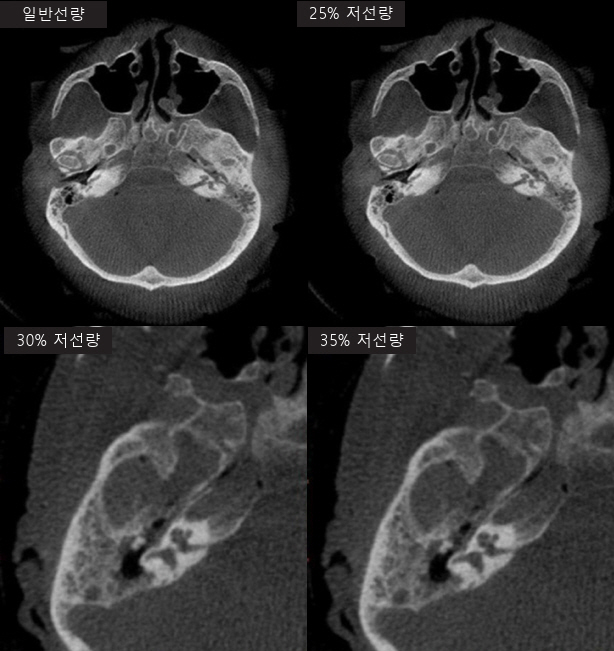

먼저, 그림 2와 같이 저선량 촬영과 노이즈 제거(Denoising)는 환자의 안전과 영상 품질 간의 균형을 맞추기 위한 핵심 영역이다. 방사선량을 줄이는 데는 X-ray 튜브에서 발생시키는 선량 자체를 제한하는 하드웨어적 접근뿐만 아니라 에지 보존필터나 BM3D(Block-Matching 3D), DnCNN(Denoising Convolutional Neural Network) 같은 고급 알고리즘을 사용하여 영상 품질을 유지‧향상시키는 소프트웨어적 접근이 함께 활용된다[7,8]. 특히 DnCNN은 다양한 임상 데이터를 학습해 노이즈를 효과적으로 억제함과 동시에 병변이나 혈관의 세부 구조를 보존하는 방향으로 발전하고 있어, 저선량 상황에서도 임상적으로 유의미한 선명도를 확보하는 데 기여하고 있다.

그림 2

C-arm X-ray 저선량 이미징 기술

출처 Reproduced from S. Ohlemeyer et al., “Cone beam CT imaging of the paranasal region with a multipurpose X-ray system-image quality and radiation exposure,” Appl. Sci., vol. 10, no. 17, 2020.